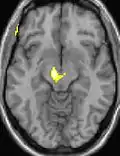

| Positron emission tomography (PET) shows brain areas being activated during pain. | ||

| Voxel-based morphometry shows brain area structural differences. | ||

Positron emission tomography (PET) scans indicate the brain areas which are activated during attack only, compared to pain free periods. These pictures show brain areas that are active during pain in yellow/orange color (called "pain matrix"). The area in the center (in all three views) is activated only during cluster headaches. The bottom row voxel-based morphometry shows structural brain differences between individuals with and without CH; only a portion of the hypothalamus is different.[36]